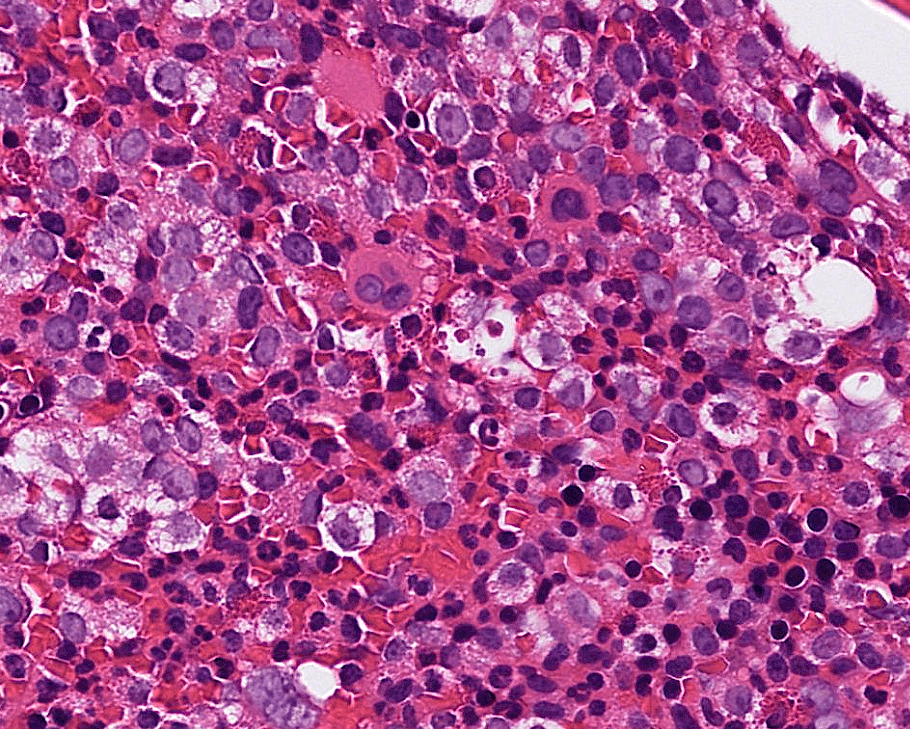

colon cancer